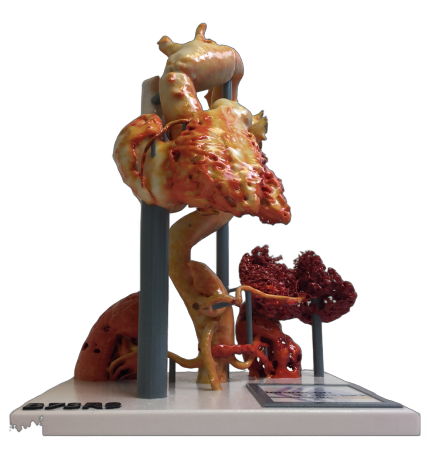

Explore Asthi's Range of 3D Printed Anatomical Models.

Asthi offers four types of models to suit a variety of surgical applications. Our coloured models provide a detailed and vivid representation of anatomical structures, while our transparent models allow for greater visibility and depth perception. Our bone-like models offer a Realistic simulation of human bone. Whether you’re a surgeon, medical student, or researcher, Asthi’s 3D-printed anatomical models offer a comprehensive solution for surgical planning and training.

Asthi - Coloured 3D Printed Models

Our coloured models are designed to provide a more visual representation of human anatomy. They are available in various colours and are perfect for medical professionals who prefer a more visual learning style. These models are great for teaching, as the different colours make it easy to identify and study specific anatomies.

Targeted Healthcare Branches

Urology

Cardiology